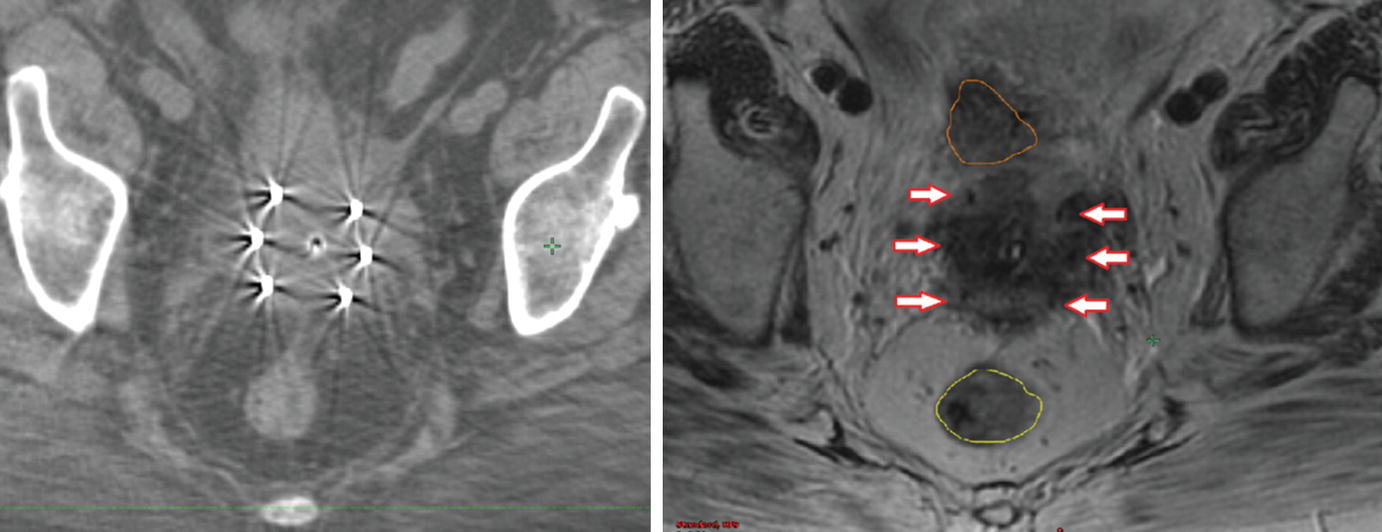

Pdf Combined Intracavitary And Interstitial Brachytherapy Of Cervical Cancer Using The Novel Hybrid Applicator Venezia Clinical Feasibility And Initial Results

Aiming For 100 Local Control In Locally Advanced Cervical Cancer The Role Of Complex Brachytherapy Applicators And Intraprocedural Imaging Sciencedirect

These patients received external beam radiation therapy delivered to 450 to 504 Gy in 25–28 fractions Intracavitary brachytherapy delivered in the T/O approach was given in four–five fractions in doses of 55–7 Gy per fraction All patients had MRI for brachytherapy planning at time of the first T/O from which HRCTV was created. Fortytwo percent of women were estimated to have inadequate tumor coverage with T O brachytherapy The GTVTinit volume and dimensions (superiorinferior, leftright, anteriorposterior) on MRI1 were all important predictive factors of inadequate coverage on multivariate analysis. What is your approach to a cervical SCC patient in which you're unable to properly place a T&O, due to obliterated cervical os, after completion of EBRT?.